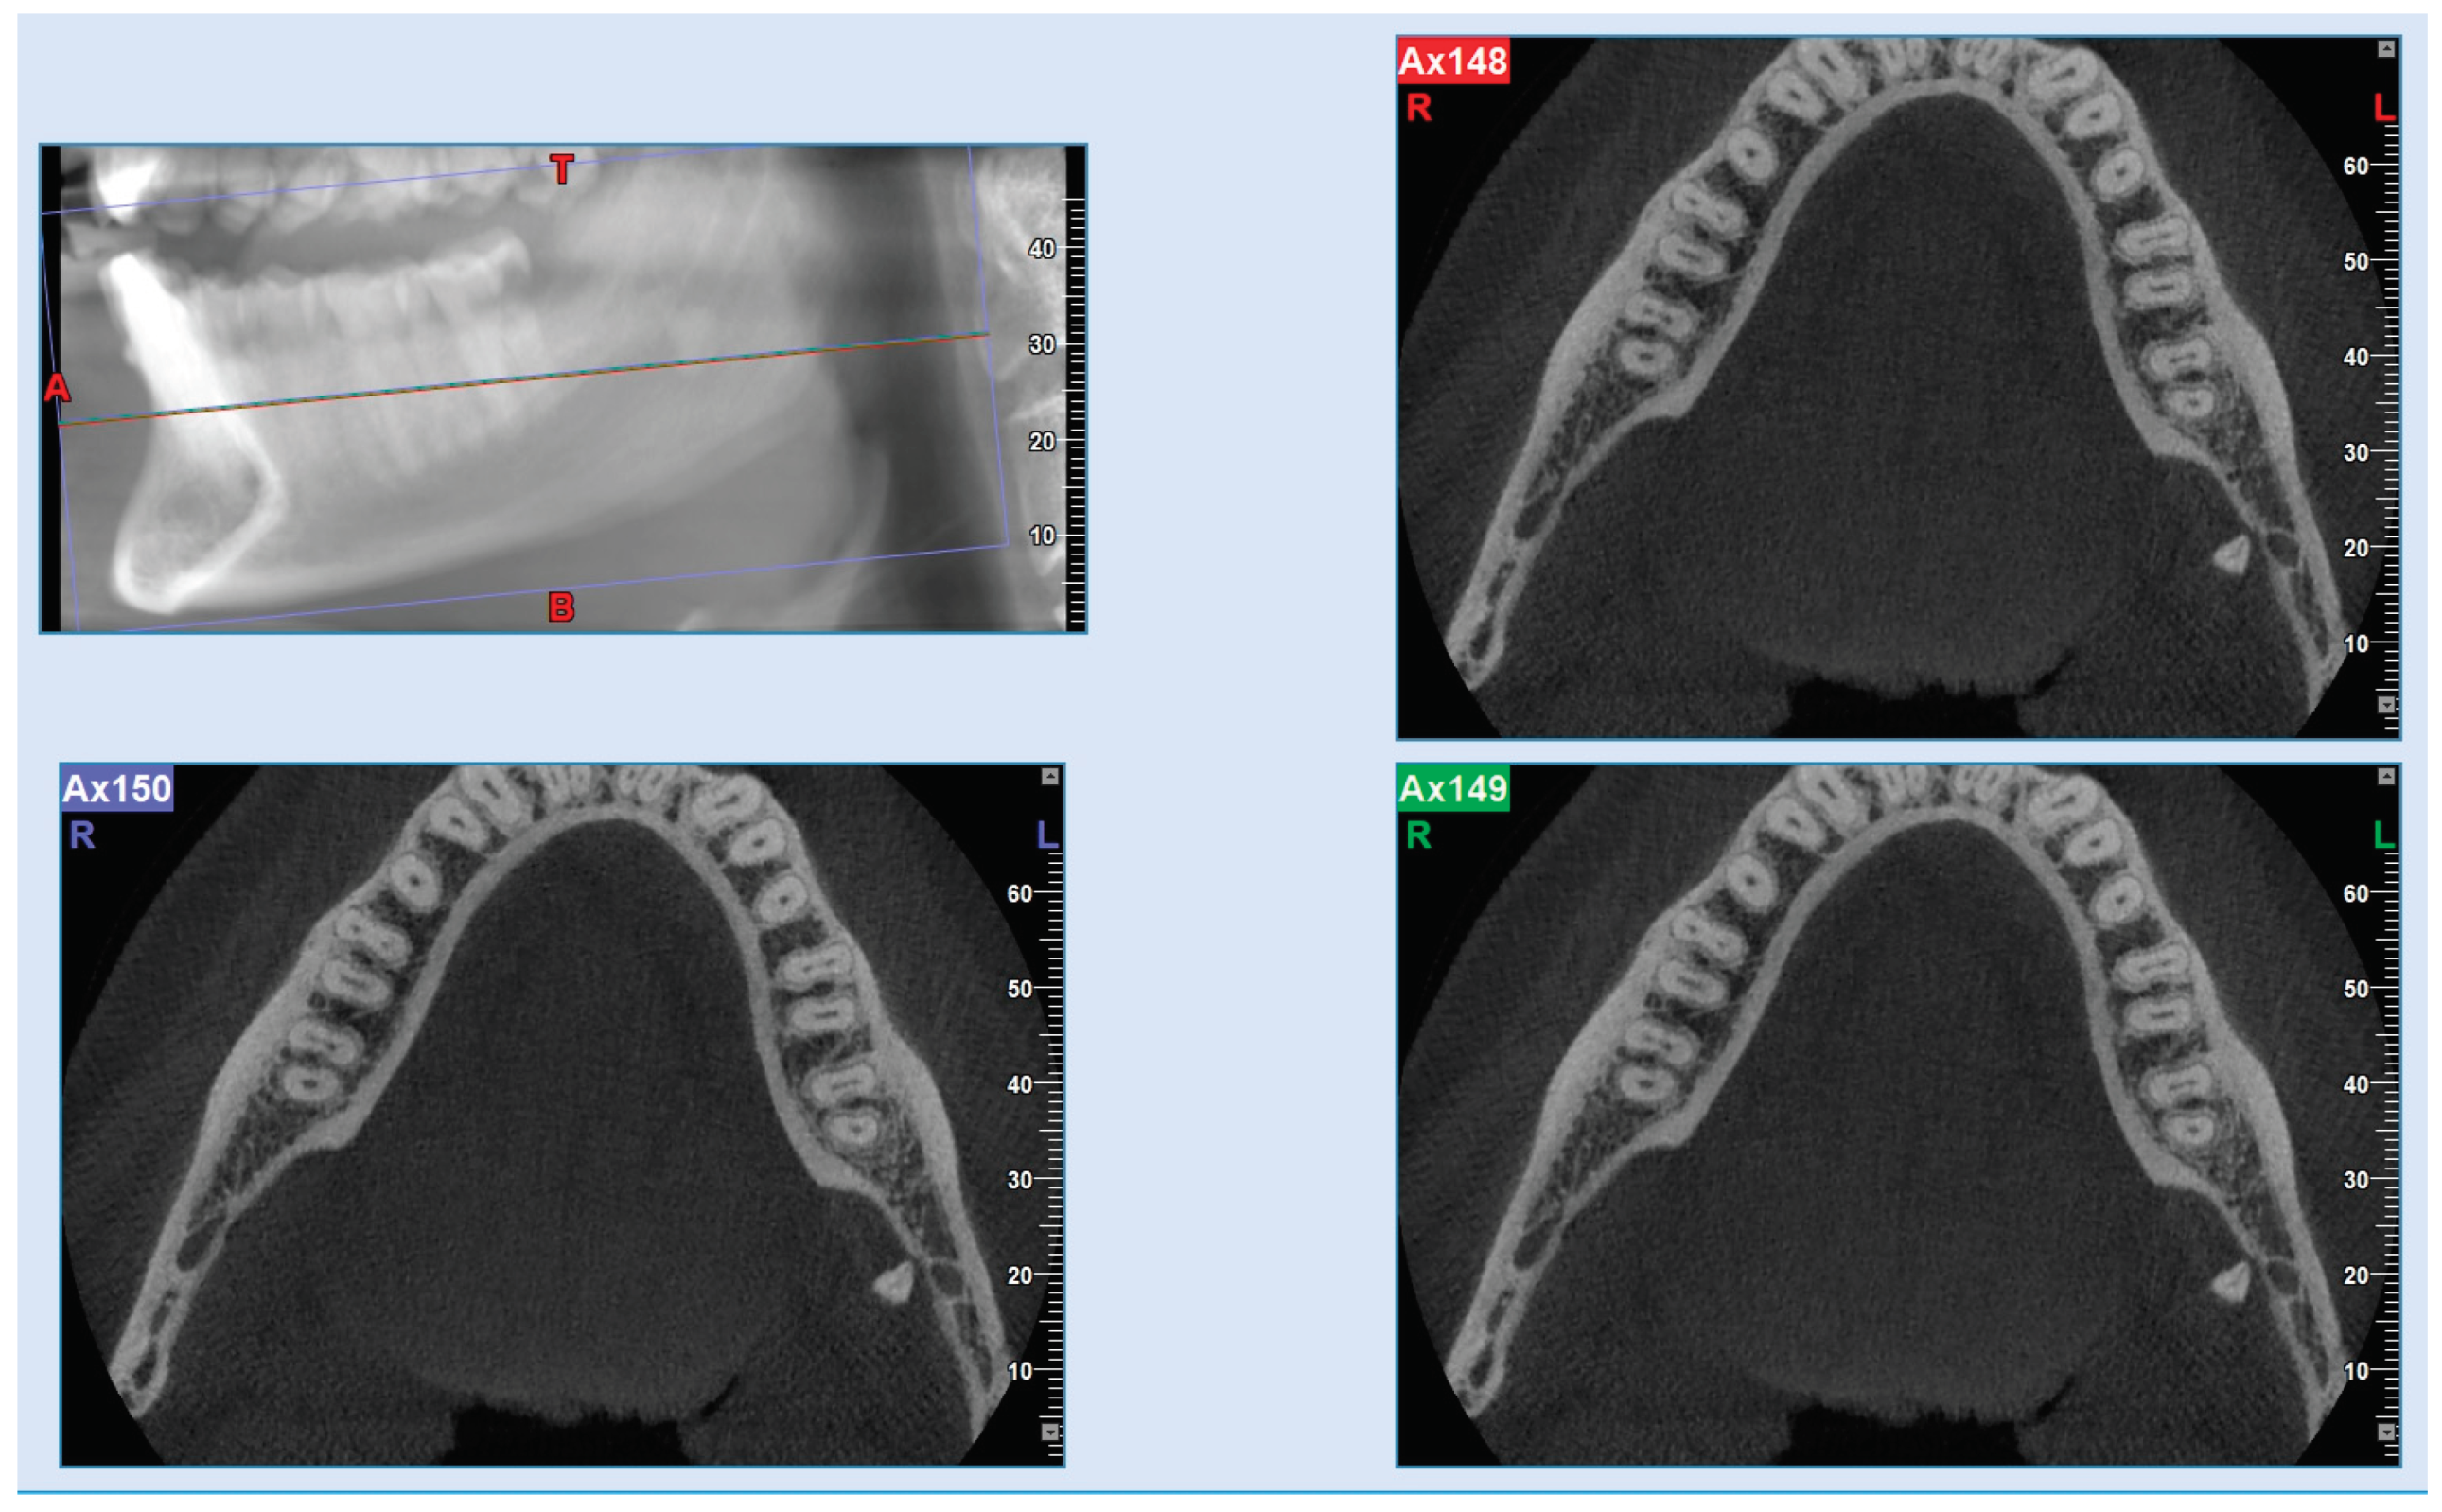

The patient showed up to our clinic with complaints following a wisdom tooth extraction. Periapical and panoramic radiographs (Figure 1) pointed to a mesially inclined and impacted tooth #38 having been recently extracted, which had caused caries in the distal portion of the adjacent tooth (tooth #37). A similar situation was observed on the opposite side; however, in that case, the wisdom tooth extraction had not led to any negative consequences. The extraction procedure was performed in March 2022, and lasted approximately two and a half hours. At the end of the procedure, the dentist took a post-operative dental radiograph (Figure 2) and informed the patient that a root fragment had not been removed. The dentist recommended a Cone-Beam CT scan to determine the fragment’s position. Following the dentist’s advice, the patient underwent a Cone-Beam CT scan at a medical center in March. On the same day, the patient returned to the dentist with the results, which showed that the root fragment had been displaced into the submandibular space (Figure 3), further necessitating a removal procedure at a hospital facility. The patient reported undergoing antibiotic and anti-inflammatory therapies for pain management and lowering the risk of infections prior to the surgery. In April 2022, the patient was admitted to the dentistry unit of a hospital where urgent maxillofacial surgery was deemed necessary. The patient was advised to consult a maxillofacial surgery specialist, who emphasized the importance of timely intervention to control the existing infection and prevent further complications caused by the dislocated root. Subsequently, the patient went to a private clinic, where a maxillofacial surgeon and their team performed the extraction of the dental root under both general and local anesthesia, as documented in the medical records provided to the patient. The procedure required a one-day hospital stay. Upon discharge, the patient was prescribed a supportive pharmacological therapy, including non-steroidal anti-inflammatory drugs (ibuprofen in a dosage of 400 mg every 4–6 h) and an antibiotic (amoxicillin with clavulanic acid in a dosage of 875 mg + 125 mg, twice daily for 5 days), as noted in the medical records.

Figure 2. Panoramic radiograph taken after the lower wisdom teeth extraction, shown on the right side the residual fractured root.